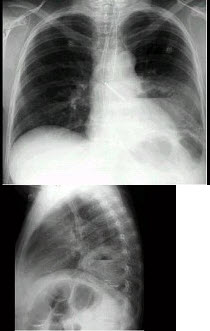

4、单项选择题

男,70岁,胸痛,不咳嗽、发热,X线检查如图,最可能的诊断是()

A.左肺结核瘤

B.左侧叶间积液

C.左肺癌

D.左肺炎性假瘤

E.左肺错构瘤